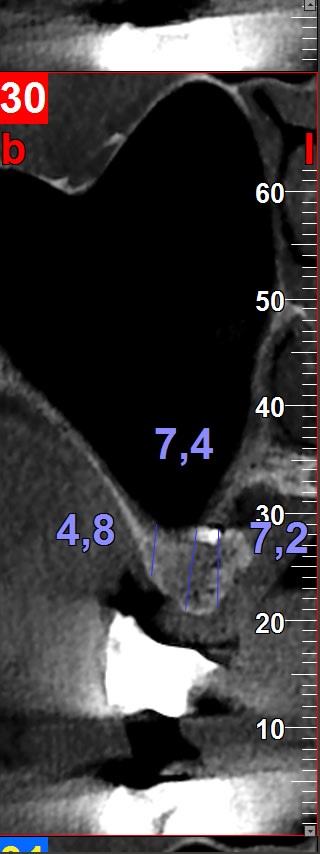

J'aurais besoin de votre avis éclairé dans la gestion de cet édentement 16 17.

La 18 est mésialée et regarde un peu en vestibulaire.

J'ai extrait la 16 suite à une fracture de racines et une infection paro.

Et maintenant se pose le problème du replacement de 16 et 17.

Par contre est ce que la mésialisation de la 18 est possible même si le sinus plonge au niveau de l'édentement de la 17 ancien et qu'il n'y a pas d'os en mésial ? Ça va se remanier tout seul ?

L'ortho sur 18, nonobstant le coût, j'aimerais bien voir comment la sagesse avance en étant déjà contre la corticale de la procidence sinusienne.

Bonsoir, je ferais comme sur l'image n°6, c'est à dire extraction 18, implant en 16 droit, implant angulé en 18 et prothétiquement une 16 et une 17. Pas de sinus, pas d'ortho. Voir 48 qui risque de poser des problèmes au niveau occlusale.